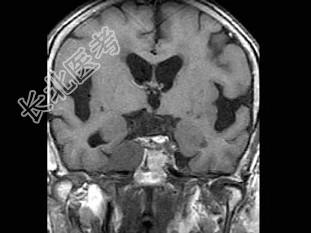

- 单项选择题男,46岁, 面部肌肉麻木、疼痛,咀嚼困难, 牙痛,MRI检查如图, 最可能的诊断是 ( )

B、三叉神经鞘瘤